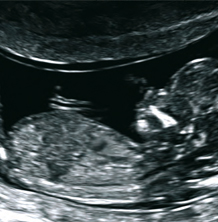

Differenzierte Ultraschalluntersuchung der Stufe DEGUM II zur weiterführenden Diagnostik und Ausschluß von Fehlbildungen, Entwicklungsstörungen und anderen Gefahrenzuständen für das ungeborene Kind. Idealer Untersuchungszeitpunkt ist der Zeitraum zwischen der 20. und 22. Schwangerschaftswoche. Bei speziellen Fragestellungen ist die Untersuchung auch in anderen Wochen möglich. Bei dieser Untersuchung wird das Kind genau vermessen (Fetometrie), alle Organe des Feten , einschließlich Gehirn und Herz, beurteilt, sowie Plazenta- und Fruchtwasserverhältnisse überprüft. Damit können bis zu 95% der schweren Fehlbildungen und Entwicklungsstörungen erkannt und ggf. behandelt werden.